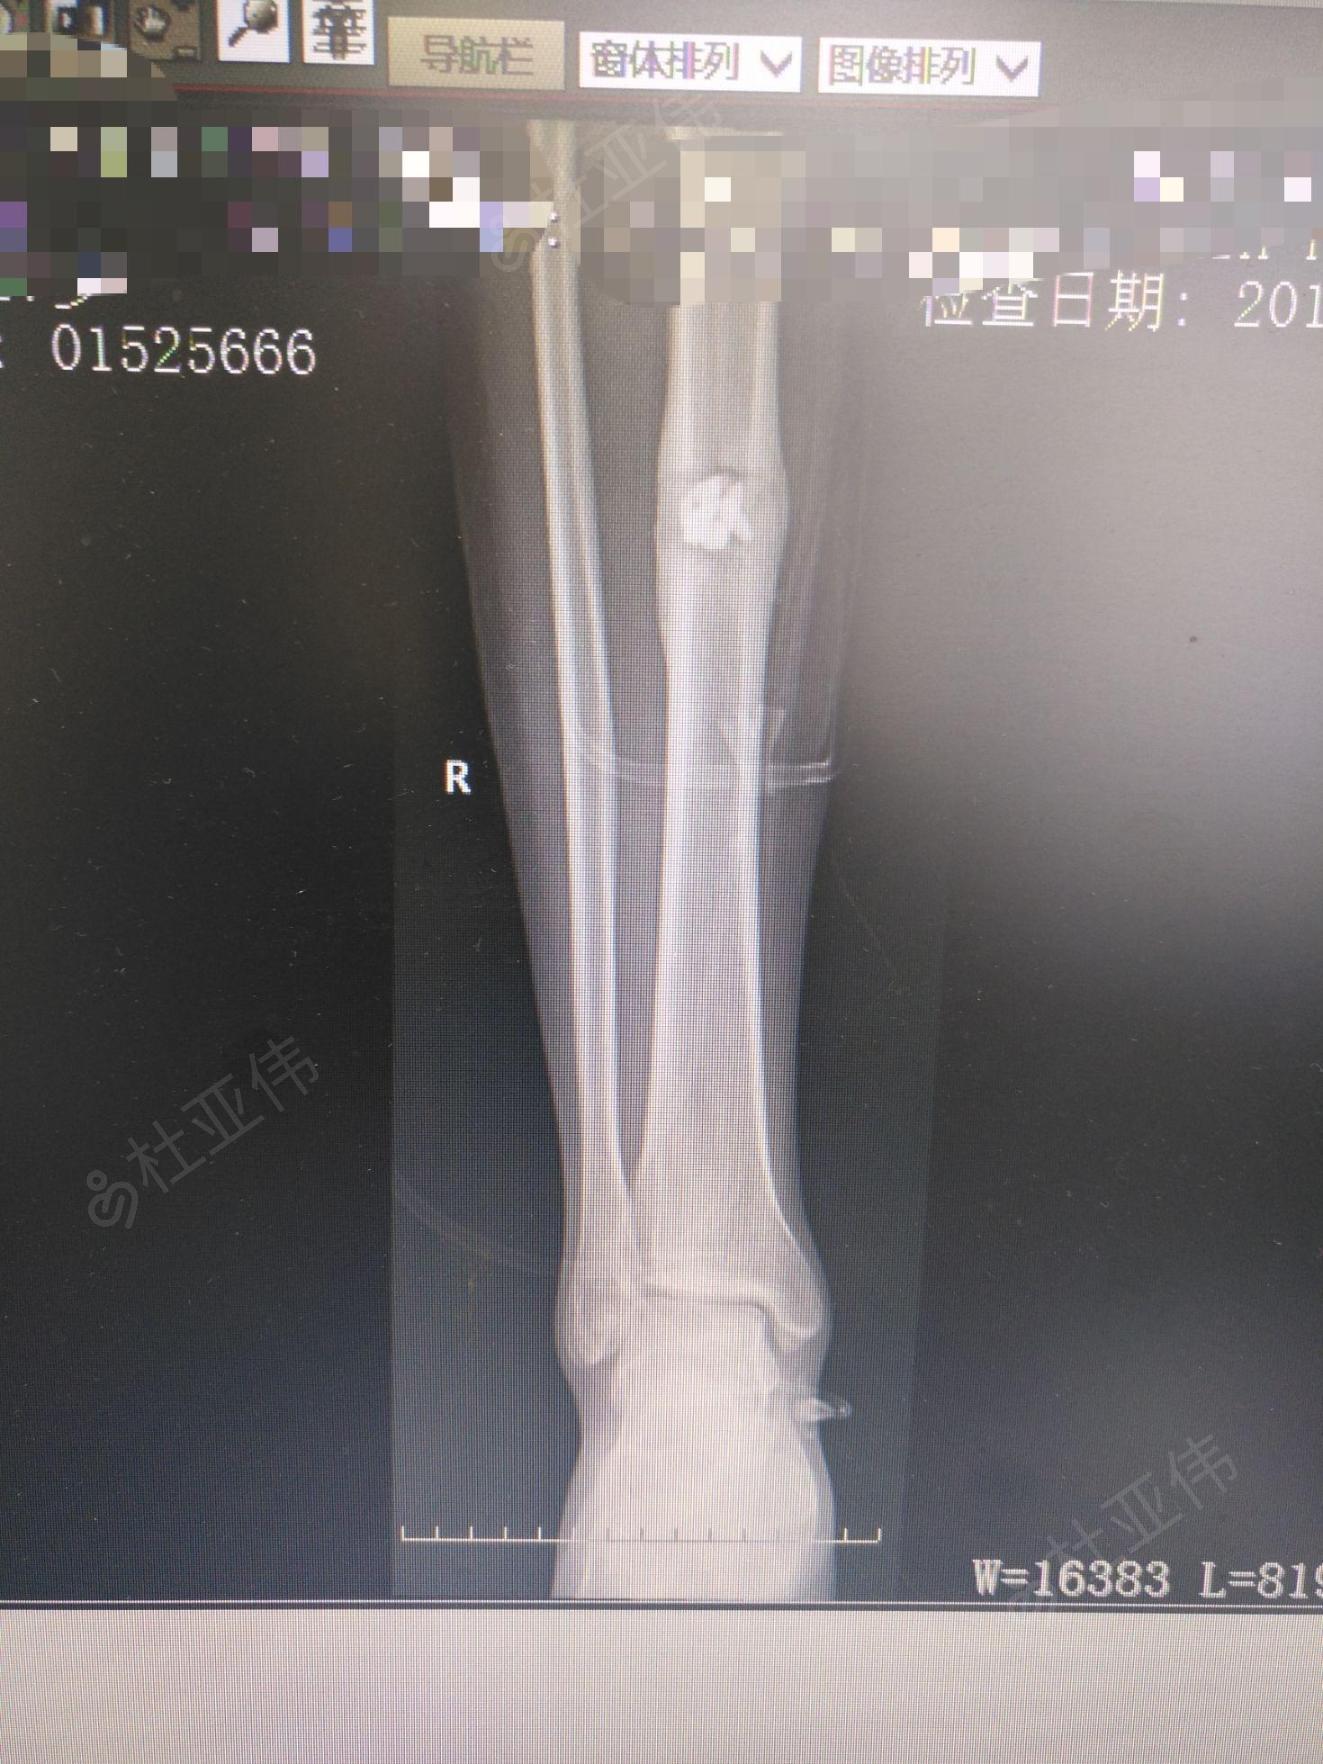

左胫骨慢性骨髓炎

年轻人x线腿显示胫骨骨髓炎照片